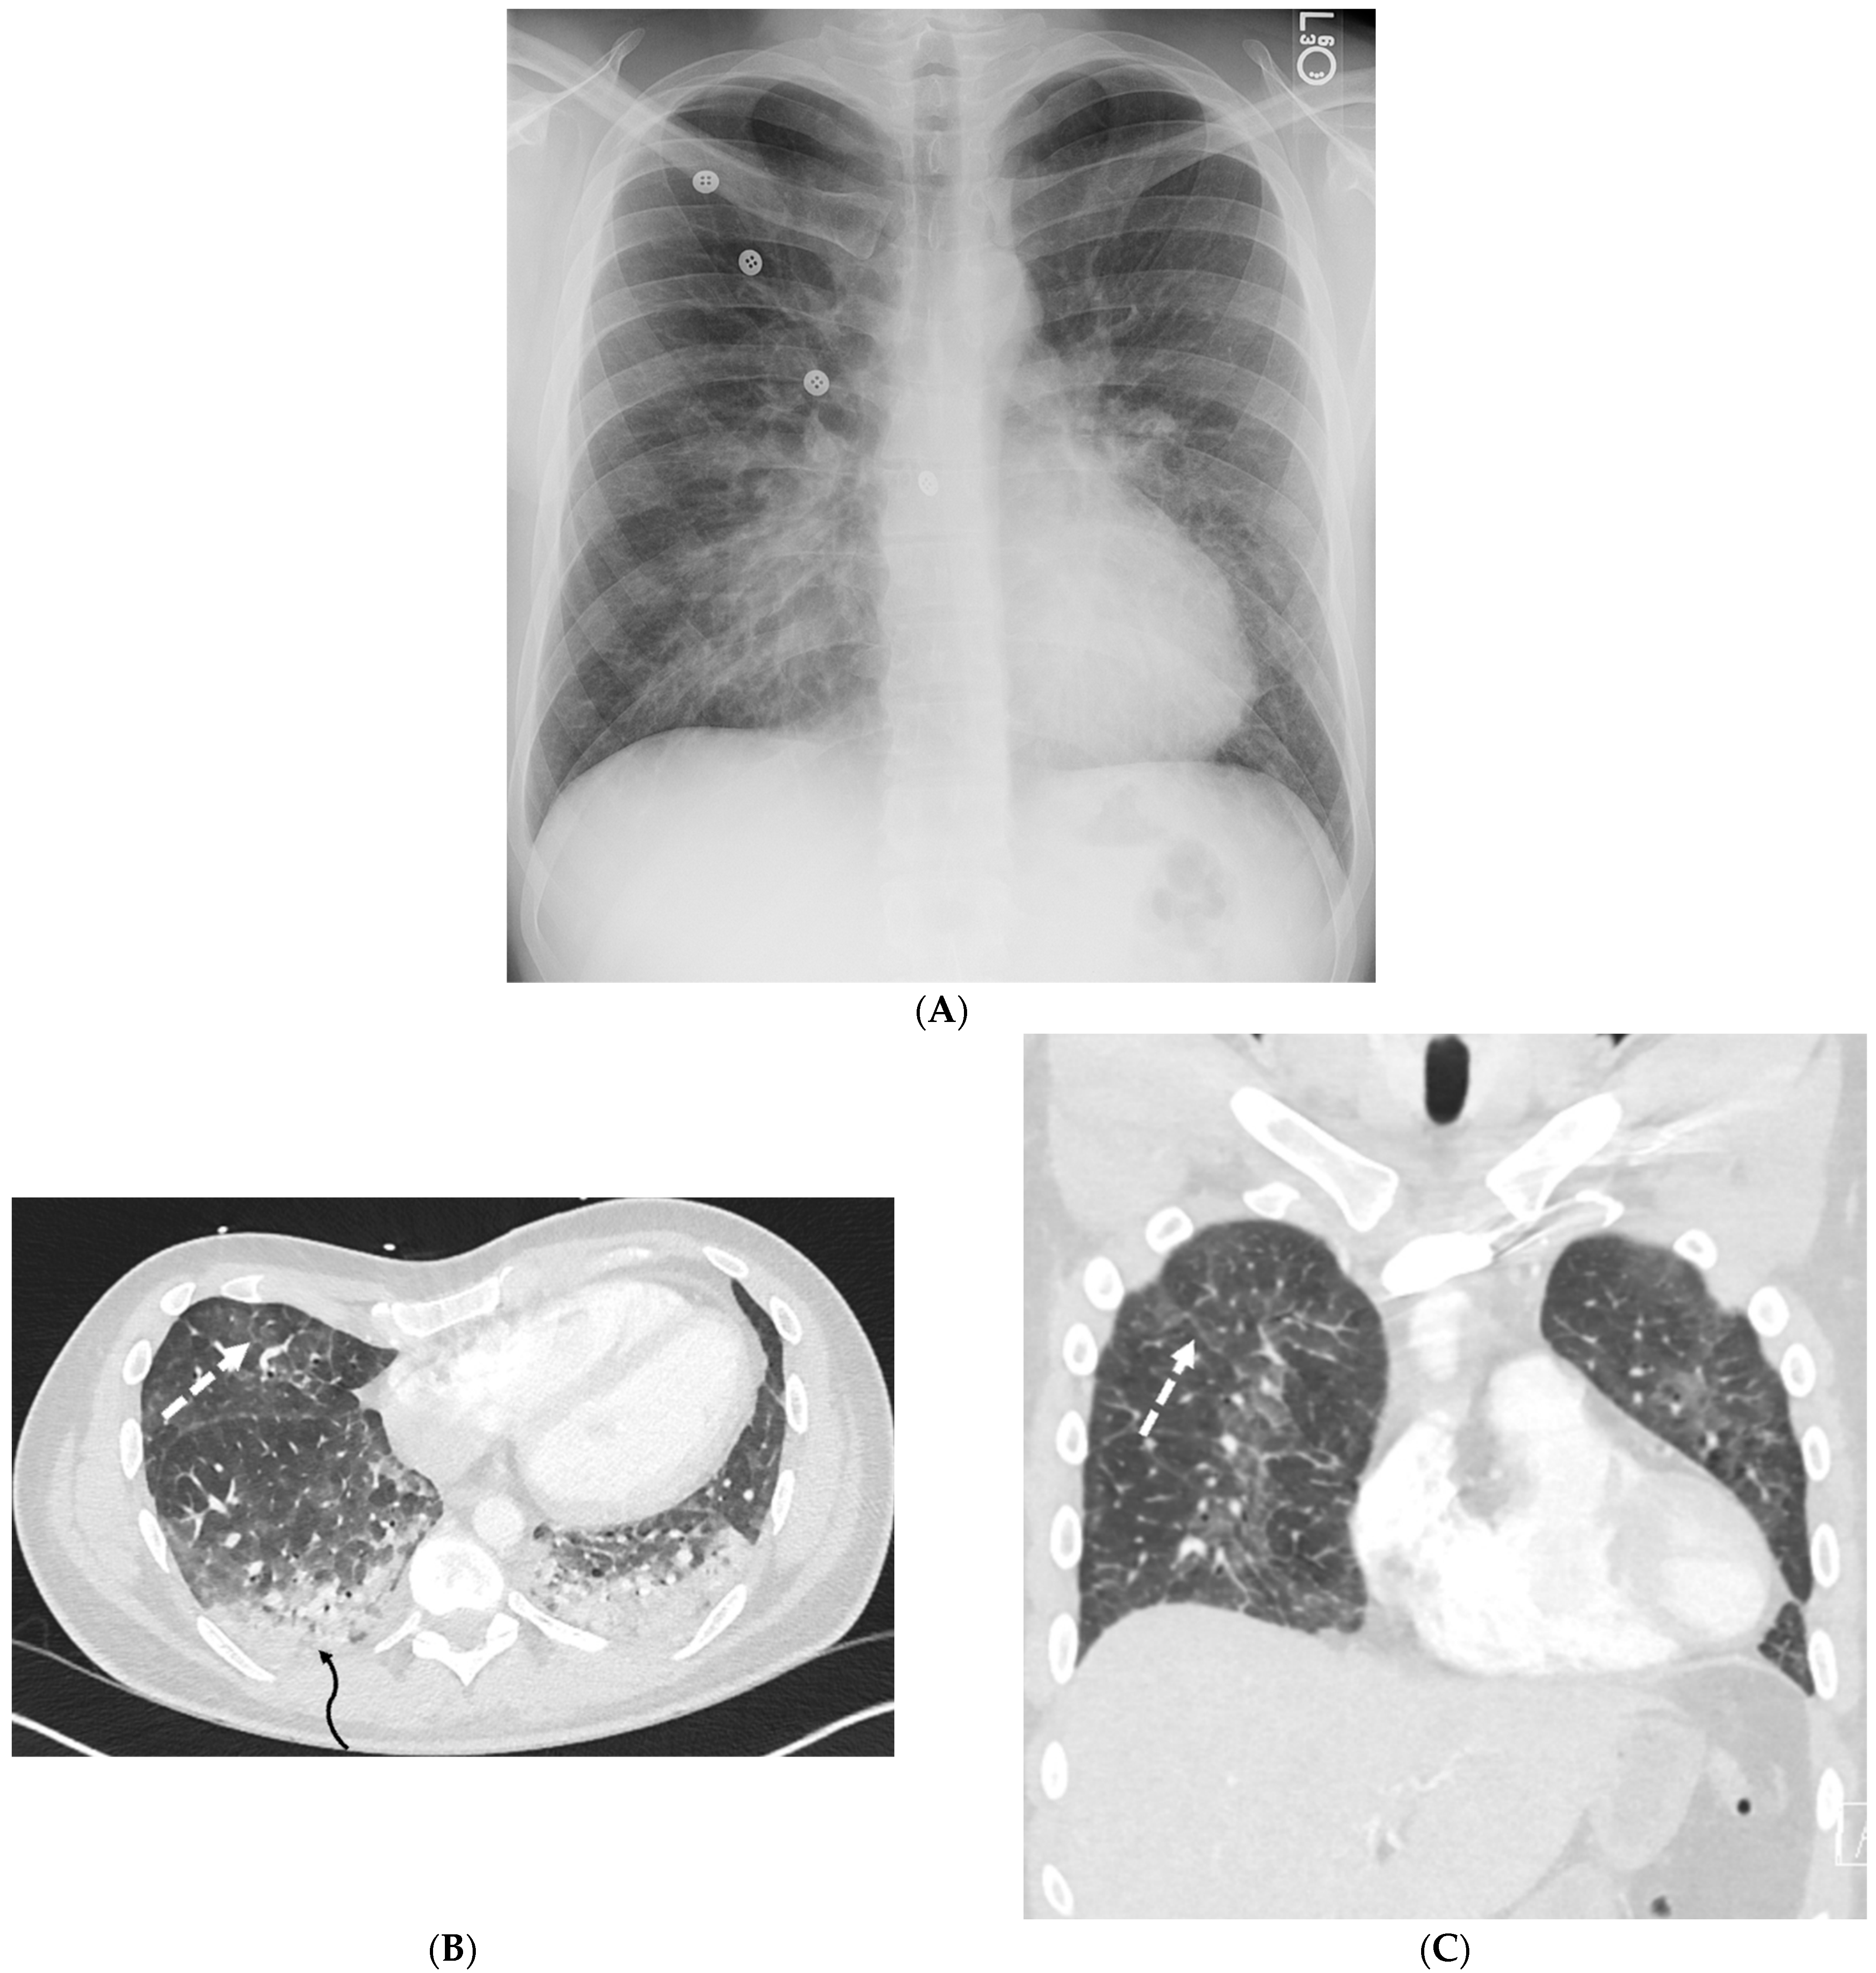

2.1. COVID-19 Pneumonia

2.2. Bacterial Pneumonia

4.7. Pulmonary Vein Stenosis (PVS)